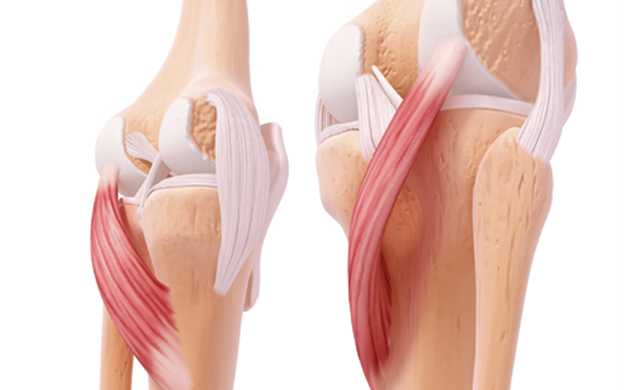

십자인대파열 (전방.후방)

십자인대는 무릎의 위 뼈와 아래 뼈가 서로 앞 뒤로 흔들리지 않도록 막아주는 역할을 하는 십자형태의 인대를 말합니다. 앞에 위치한 인대를 전방십자인대, 뒤에 위치한 인대를 후방십자인대라고 하며 무릎관절이 과도하게 회전하는 것을 방지하고 무릎관절이 뒤로 꺾이는 것을 막아주는 역할을 합니다. 십자인대파열은 무릎관절을 과도하게 움직이거나 부상을 당하게 되면서 십자인대가 손상을 입거나 파열되는 질환을 말합니다.

반월상연골판파열

반월상연골판은 무릎의 연골 사이에 발생하는 마찰을 줄여주며 체중을 흡수하여 하중을 분산시키고 관절의 운동성과 안정성을 유지하는 역할을 합니다. 이 반월상연골판은 연골 중에서도 강한 편에 속하지만 강한 외부의 충격이나 반복적인 무릎사용, 손상 등의 원인으로 찢어지거나 파열되어 무릎통증이 발생하게 됩니다.